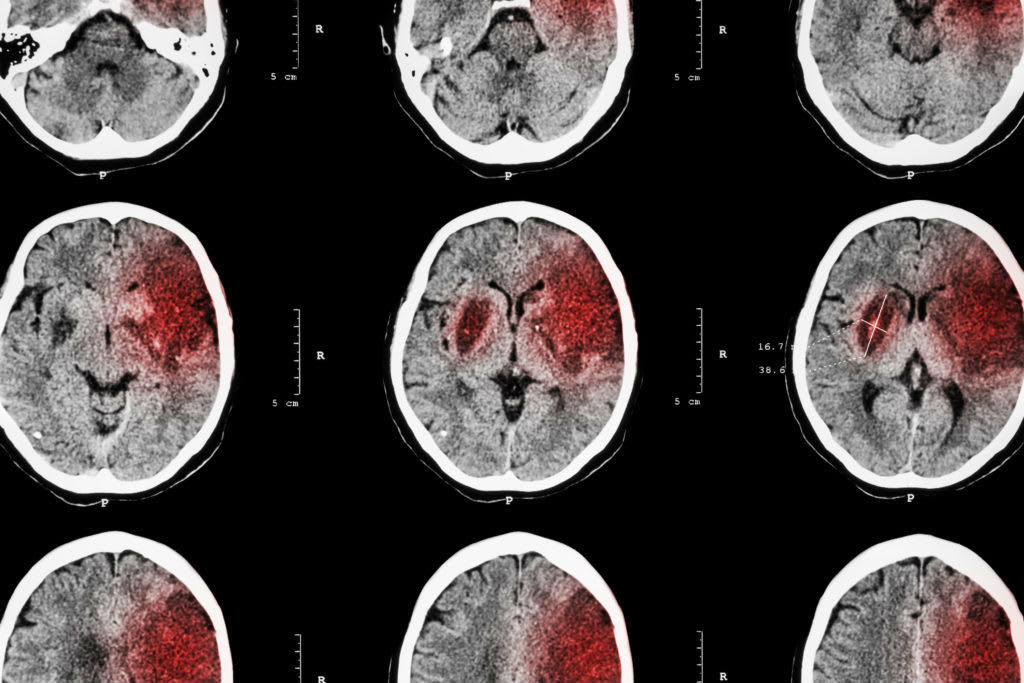

Five days went by and the doctors were unsure of why I had not woke up. Doctors decided to do another scan of my brain to see if maybe I had more than just a concussion... this is when they noticed the bleeding in the front right portion of my brain. This hospital visit transitioned into a waiting game for my family. Two more days went by, and on day eight I finally came to, and the bleeding had stopped.